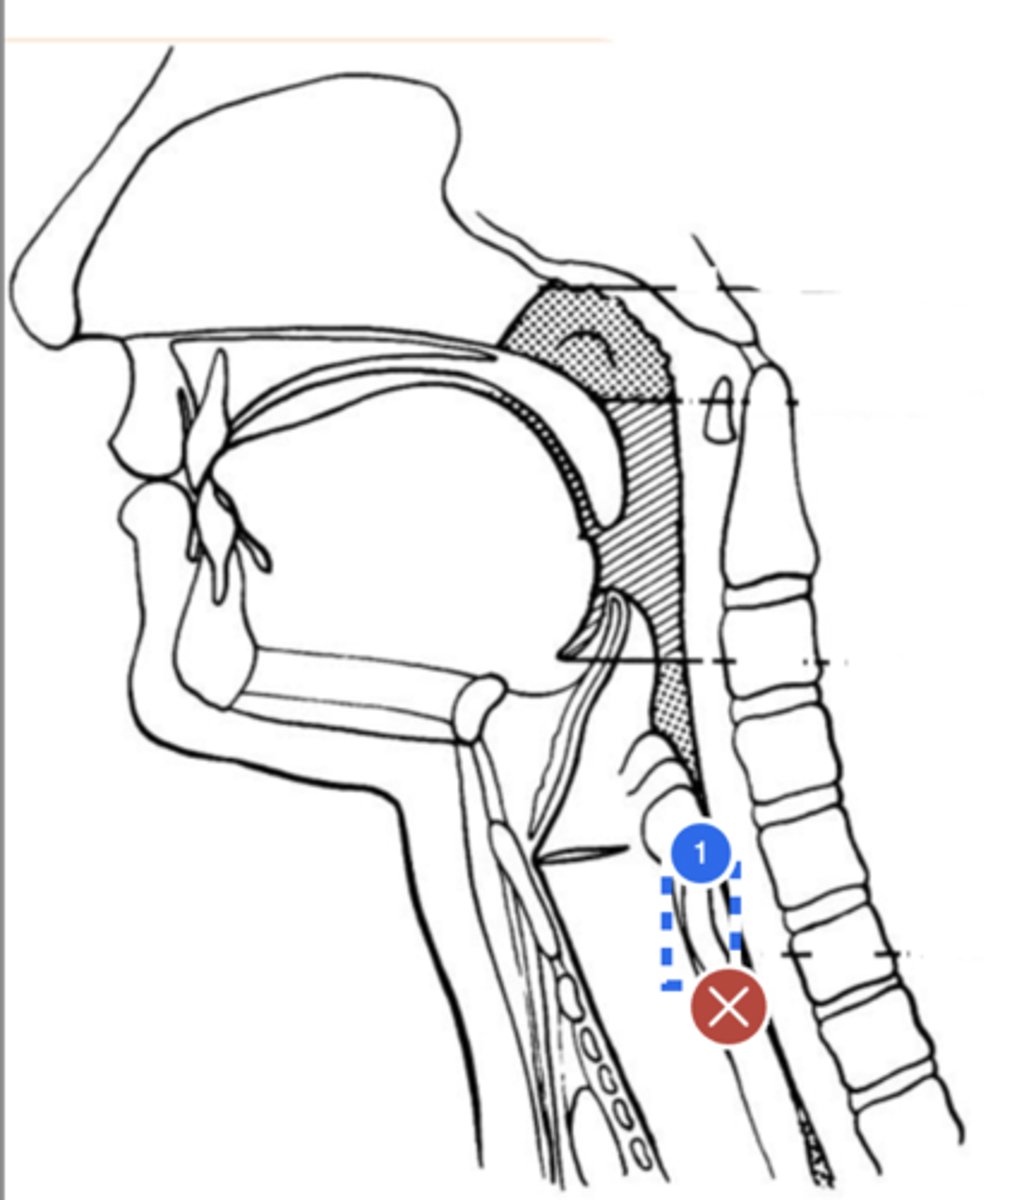

Label base of tongue (lateral view)

label anterior tongue (lateral view)

Label posterior/ back of tongue (lateral view)

Label Mandible (lateral view)

Label velum/ soft palate (lateral view)

Label hyoid bone (lateral view)

Label epiglottis (lateral view)

Label thyroid cartilage (lateral view)

Label posterior cricoid (lateral view)

Label trachea (lateral view)

Label upper esophageal sphincter (lateral view)

Label esophagus (lateral view)

Label posterior pharyngeal wall (lateral view)